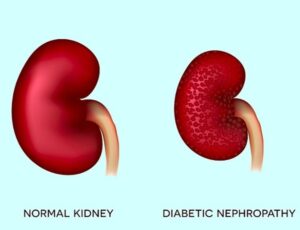

نفروپاتی دیابتی (Diabetic Nephropathy) یکی از مهمترین عوارض مزمن دیابت است که به مرور زمان باعث آسیب به واحدهای تصفیهکننده کلیه (نفرونها) میشود. این وضعیت در صورت عدم کنترل قند خون میتواند منجر به نارسایی کلیه، نیاز به دیالیز یا پیوند کلیه شود. آگاهی از چگونگی تأثیر دیابت بر کلیهها و انجام اقدامات پیشگیرانه، نقشی اساسی در حفظ سلامت کلیهها دارد.

مراحل پیشرفت آسیب کلیوی در دیابت

نفروپاتی دیابتی معمولاً بهصورت تدریجی و در پنج مرحله پیشرفت میکند:

1. افزایش فیلتراسیون اولیه (Hyperfiltration) – کلیهها بیش از حد کار میکنند.

2. میکروآلبومینوری – مقدار کمی آلبومین در ادرار ظاهر میشود.

3. ماکروآلبومینوری – میزان قابلتوجهی پروتئین در ادرار وجود دارد.

4. کاهش عملکرد کلیه (افت GFR) – دفع مواد زائد مختل میشود.

5. نارسایی کلیه یا ESRD – ممکن است نیاز به دیالیز یا پیوند کلیه باشد.

نفروپاتی دیابتی از مهمترین عوارض طولانیمدت دیابت است که در اثر بالا بودن قند خون، فشار خون و التهاب کلیه ایجاد میشود. تشخیص زودهنگام از طریق آزمایش آلبومین و نظارت بر عملکرد کلیه، کلید پیشگیری از نارسایی است. حفظ قند خون هدف، کنترل فشار خون و سبک زندگی سالم میتواند عملکرد کلیه را برای سالها پایدار نگه دارد و خطر دیالیز را کاهش دهد.